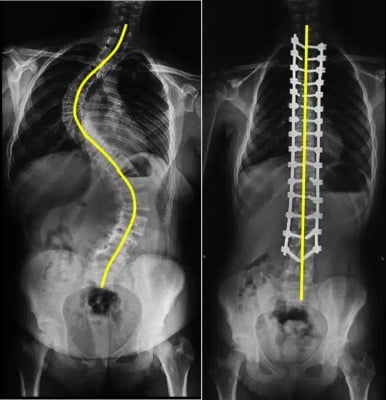

A straight spine is crucial for maintaining balance, promoting movement, and ensuring overall body alignment. However, in scoliosis, the spine curves abnormally (often in an “S” or “C” shape), resulting in uneven shoulders, back pain, and postural changes. While doctors manage mild scoliosis with observation or braces, more severe curves often require surgery to correct the deformity and prevent long-term complications.

Scoliosis surgery is a specialized orthopedic or spinal procedure that straightens and stabilizes the spine using metal rods, screws, and bone grafts. The goal is not only to correct the spinal curve but also to prevent it from worsening and restore proper alignment, thereby improving balance and lung function.

Scoliosis is a structural deformity of the spine in which the backbone curves sideways, often forming an “S” or “C” shape. The condition can develop during growth in childhood or adolescence, though it may also appear in adults due to degenerative changes or previous spinal injuries.

In a healthy spine, the vertebrae are stacked vertically, allowing balanced posture and movement. In scoliosis, the vertebrae rotate and tilt abnormally, causing the shoulders or hips to appear uneven. The severity of curvature is measured in degrees using the Cobb angle, which helps doctors decide whether observation, bracing, or surgery is required.

- Screw and Rod Placement: Surgeons insert special pedicle screws into the vertebrae. These screws act as anchors for metal rods that will realign the spine. The rods are carefully attached and adjusted to straighten the curve gradually.

- Spinal Fusion: Bone grafts are placed along the spine. Over time, these grafts fuse the vertebrae, creating a solid and stable bone structure that maintains correction permanently.